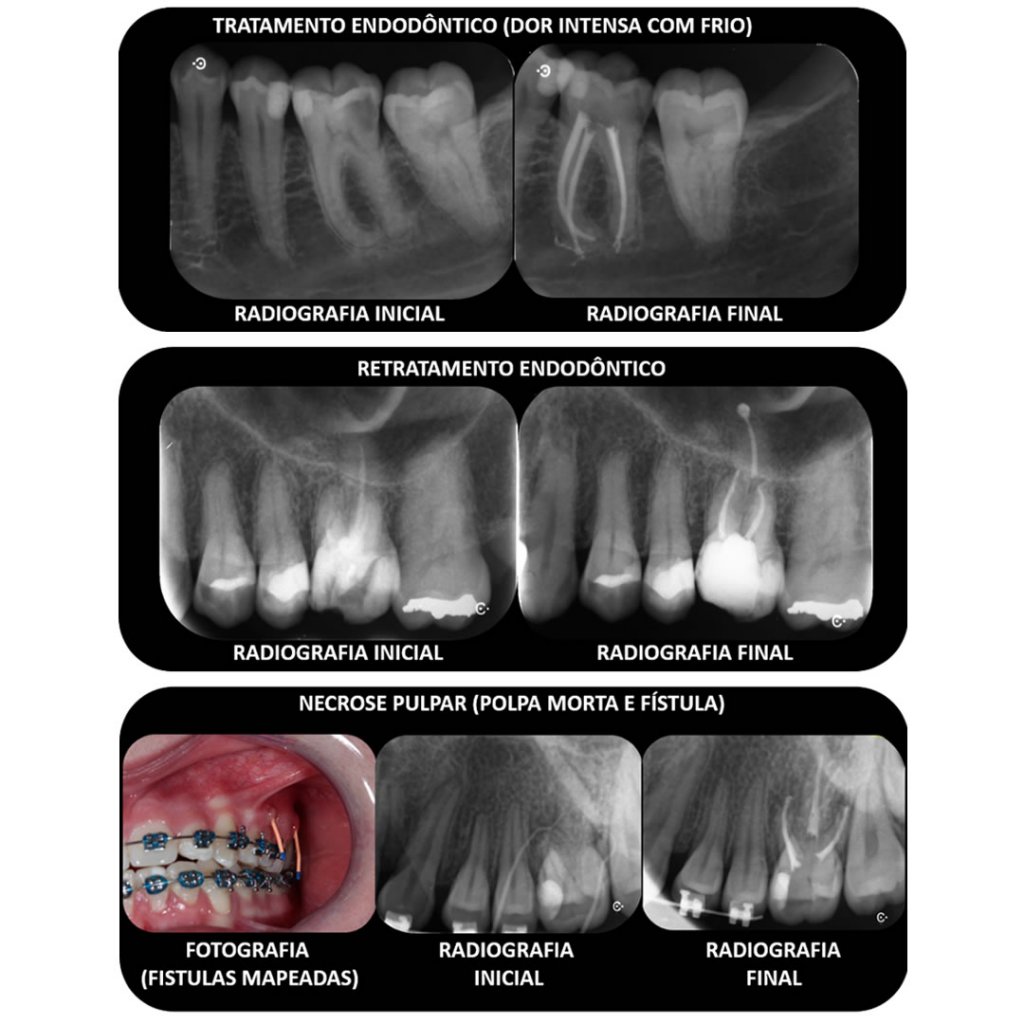

Tratamento Endodôntico

Especialidade que trata da parte interna do dente, popularmente conhecido como o canal, ou o nervo. São executados tratamentos em função da dor, de escurecimento, aparecimento de fistula ou bolinhas em cima dos dentes ou ainda retratamentos nos dentes que necessitam desses procedimentos.

Muitas vezes, o dente não dói, não tem qualquer problema visível e a necessidade de tratamento endodôntico é detectada por um exame de radiografias, que demonstra uma lesão periapical.

Porém, a dor com frio ou calor também pode ser sinal de que o dente está doente e precisa ser tratado.

Esse tratamento é executado por um especialista em Endodontia.